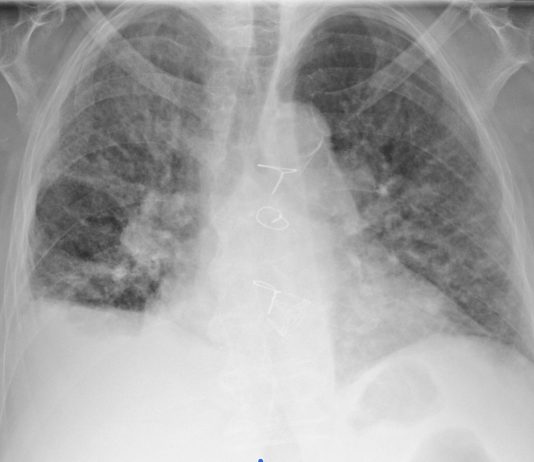

68-year-old male

with fever, dyspnea and diarrhea for 7 days. Blood test: leukocytosis, increased C-PR, procalcitonin in

the range. Medical history: chronic lymphocytic leukemia under follow-up,

dyslipidemia and HTA.

Chest radiography: